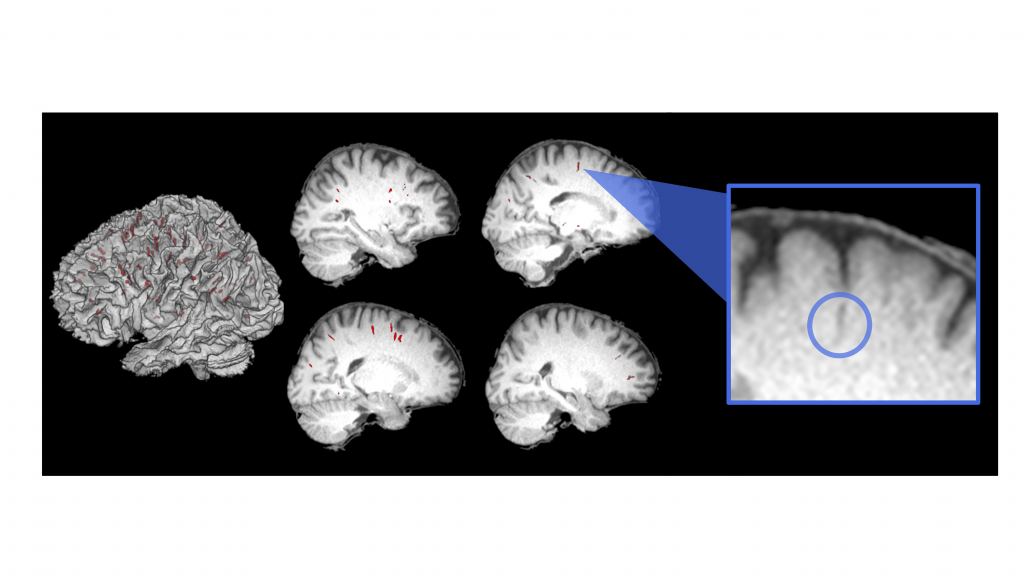

Piantino and a group of researchers just published a study called "Longitudinal MRI-visible perivascular (PVS) changes with long-duration spaceflight". In it, they discuss obvious brain changes in astronauts. "These findings have important implications as we continue space exploration," said Piantino, in a press release statement. "It also forces you to think about some basic fundamental questions of science and how life evolved here on Earth."

Researchers decided to find out by measuring the perivascular spaces in astronaut brains. These are where cerebrospinal fluid flows in the brain. They are part of a system-wide brain cleansing that occurs during sleep called the "glymphatic system". Among other things, it clears metabolic proteins that would otherwise build up in the brain. Scientists say this system seems to perform optimally during deep sleep. So, the question was: how would it change in space?

Piantino and his collaborators examined magnetic resonance imaging scans of 15 astronauts both before and after their extended stays on the International Space Station. Each space traveler had several scans: one before launch and one after they got back home on Earth. Then, they had additional scans one, three, and six months after their missions. All those MRIs got compared to the brains of people who had never been to space.

The differences were pretty interesting, and a bit unexpected in one way. The brains of first-time space travelers showed increases in the perivascular spaces. The brains of old-timers (who had been to space before) didn't show that kind of change. It's fairly clear to Piantino and the team that the experienced space fliers had somehow adapted. They aren't quite sure why. So, that will take further study.